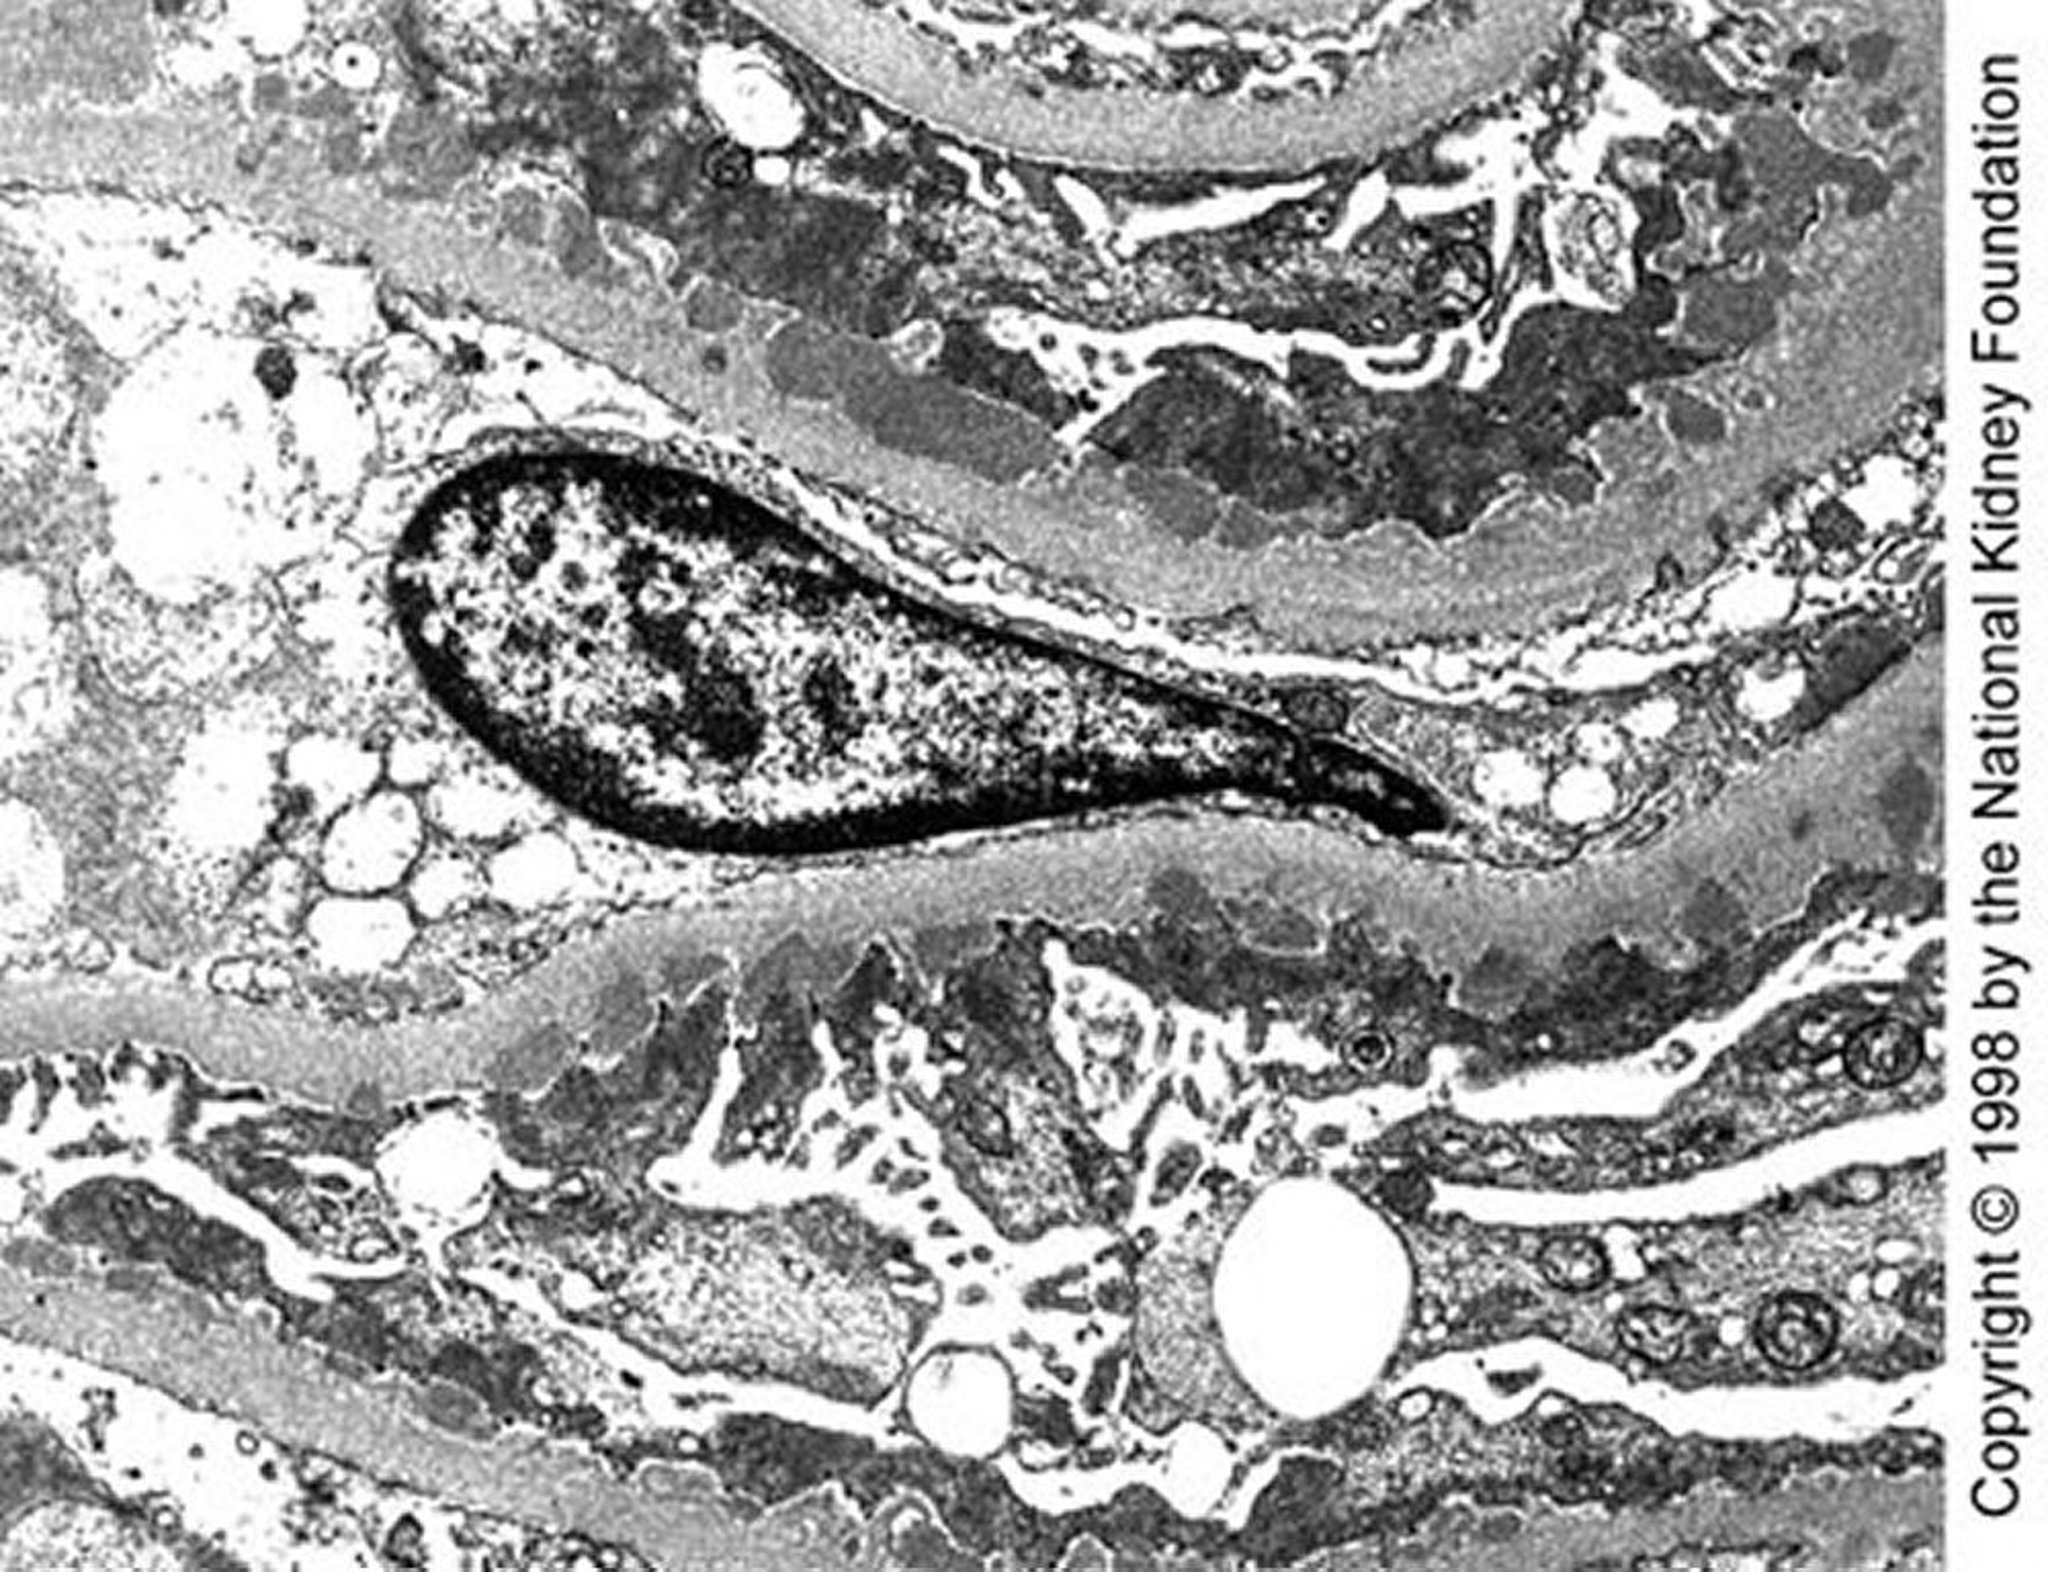

膜性腎症(高電子密度沈着物)

ステージI後期の透過型電子顕微鏡像で,上皮下に中等大の高電子密度沈着物が認められる(10,200倍)。

Image provided by Agnes Fogo, MD, and the American Journal of Kidney Diseases' Atlas of Renal Pathology (see www.ajkd.org).